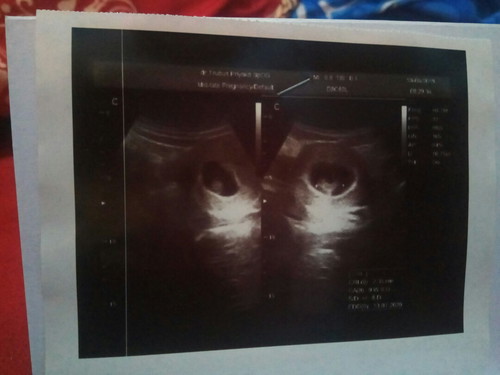

Pagi bunda :) Ini aku USG pas masuk 10 minggu kehamilan :) Tapi kata dokternya kandungan aku lemah :( Apa gara gara pas mudik naik motor? Disini bunda ada yang pernah ngalamin kandungan lemah ga?